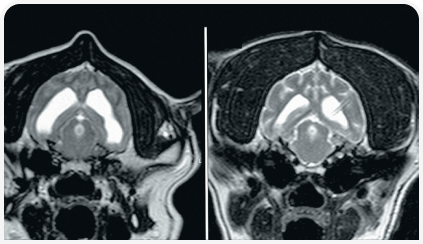

Диагноз ставится на основании изменения размера и формы черепа, неврологических признаков заболевания и нейровизуализации.

Практичным методом визуализации боковых желудочков является ультразвуковое исследование через открытый родничок.